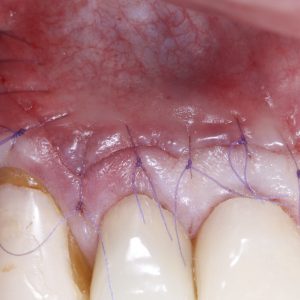

Soft tissue management: incisions and flap design. Sutures.

Hands-on Sutures

Highlights from past editions